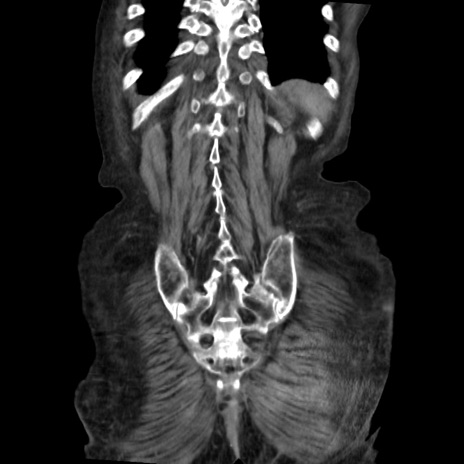

矢状断像